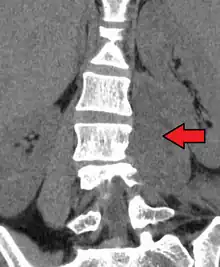

| Paraspinal abscess in the psoas muscle | |

Psoas abscess is a collection of pus in the iliopsoas muscle compartment.[1][2] It can be classified into primary psoas abscess (caused by hematogenous or lymphatic spread of a pathogen) and secondary psoas abscess (resulting from contiguous spread from an adjacent infectious focus).[2]

Psoas abscess may be caused by lumbar tuberculosis. Owing to the proximal attachments of the iliopsoas, such an abscess may drain inferiorly into the upper medial thigh and present as a swelling in the region. The sheath of the muscle arises from the lumbar vertebrae and the intervertebral discs between the vertebrae. The disc is more susceptible to infection, from tuberculosis and Salmonella discitis. The infection can spread into the psoas muscle sheath.[3]